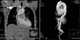

Ascending aortic dissection

Aortic dissection (AD) occurs when an injury to the innermost layer of the aorta allows blood to flow between the layers of the aortic wall, forcing the layers apart. In most cases, this is associated with a sudden onset of severe chest or back pain, often described as "tearing" in character. [Source: Wikipedia ]